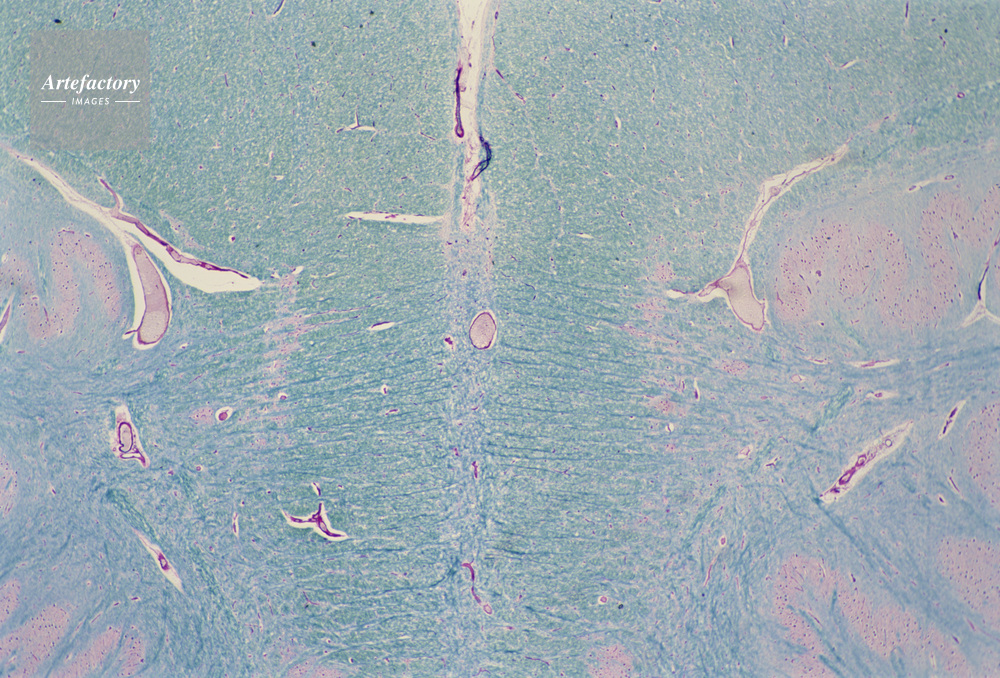

| 作品タイトル | 顕微鏡写真 | モデルリリース | なし | |

| キャプション | 骨髄,人間,10倍 | 制限事項 | ||